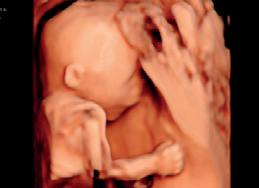

Vi er i Abs, en liten landsby nordvest i Jemen. Sykehuset vårt er det eneste i et område som dekker én million innbyggere. Det drives av både Leger Uten Grenser (MSF) og helsemyndig hetene. Kvinneklinikken, som jeg jobber på, har mellom 1200 og 1500 fødsler i måneden. Det er enkle forhold, men vi har det vi trenger; et bærbart ultralydapparat, tre doppler-apparater for å lytte til fosterlyden, en velfungerende blodbank og tilgang til et laboratorium, som utfører basale biokjemiske analyser (elektro lytter, kreatinin, ALAT, ASAT) og diagnostikk på infeksjons sykdommer som malaria, hepatitt, og HIV.